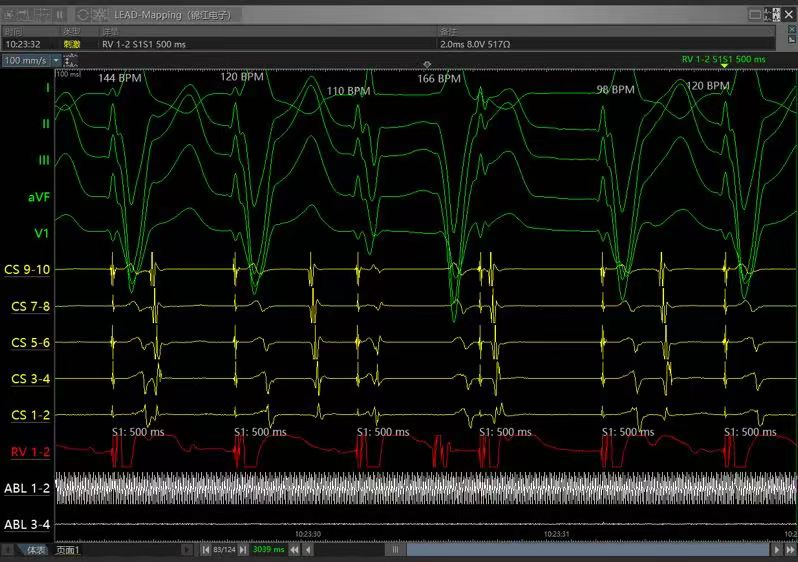

心室刺激排除旁道

跳跃和回波